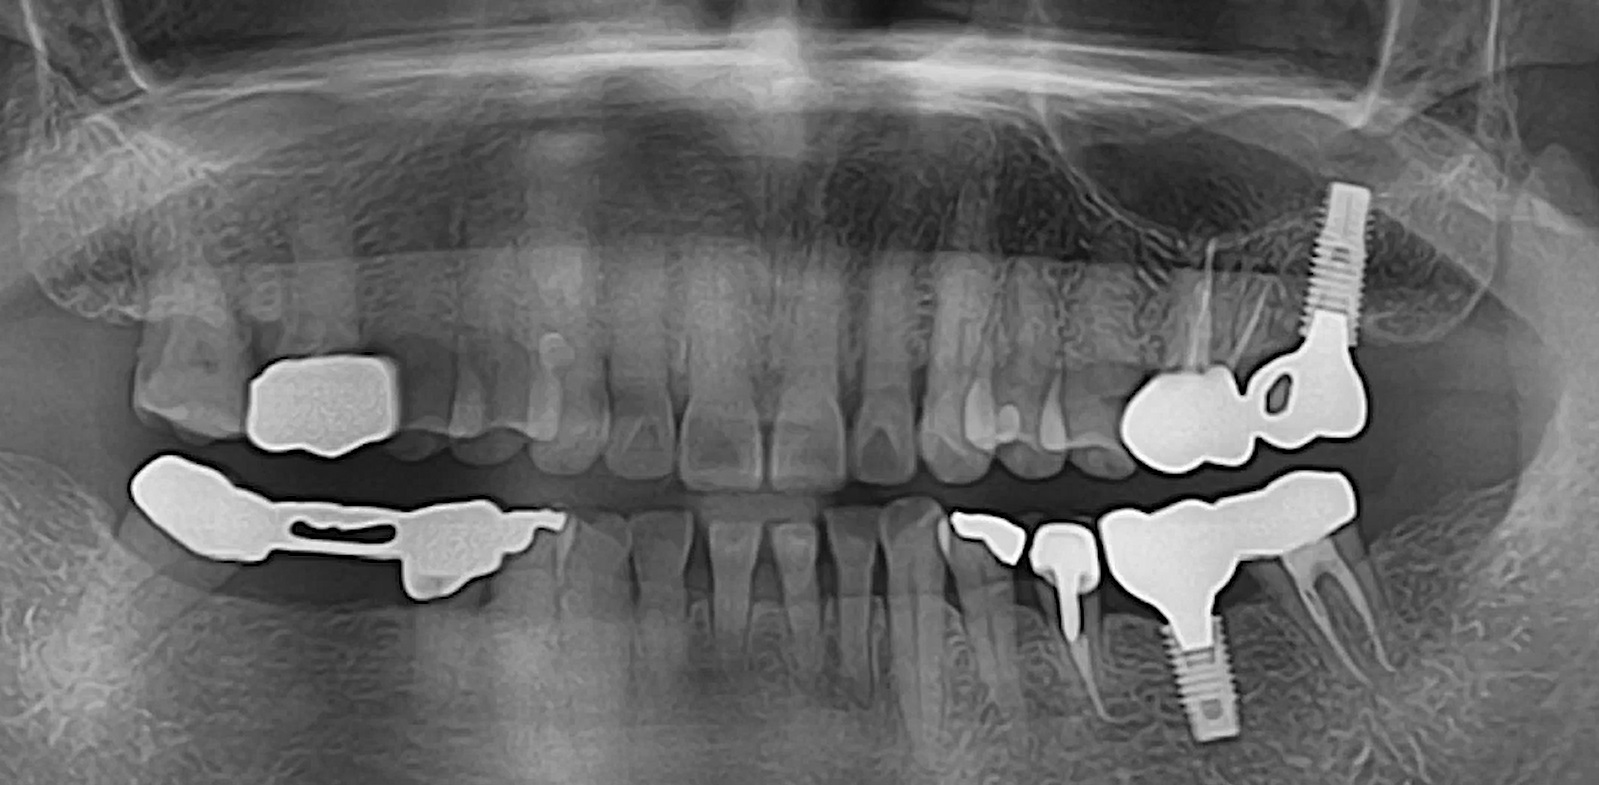

All on six R2GATE Guide Surgery

#11,#13,#16,#21,#23,#26,Digital full mouth prosthetics,Digital Guided Surgery,Edentulous,Flapless,MEG Engine,MEG-TORQ,MEGA ISQ,R2GATE Guide,R2GATE Surgical Kit(AnyRidge),video